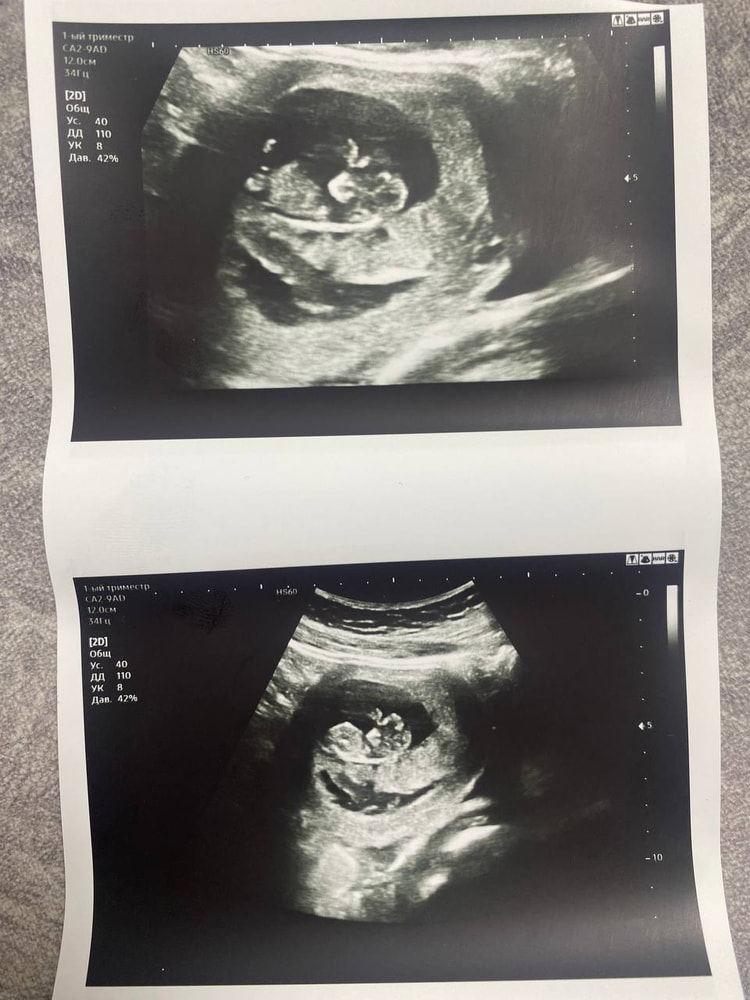

Идет 10 неделя наконец-то удалось с мужем попасть на узи

Ну что на узи нам поставили 10 недель и 3 дня опережаем на неделю! Пошла просто посмотреть и наконец-то нашему папочке показать малыша, первый раз для него такое чудо было (до этого не получалось пойти вместе на узи)! Ощущения не передаваемые! Малыш активно двигался, за что муж немного ругался в хорошем смысле на меня, что мы его разбудили и потревожили! Уверен что будет мальчик))) все идет у нас хорошо ЧСС 150 уд. мин, ктр 3,4! (4 декабря ктр 19 мм) Ни каких нареканий у врача не было! Поскольку встала на учет сдала все анализы, практически всех врачей прошла, тоже все хорошо! В это раз на узи малыш не захотел позировать для фото, но нам ручки и ножки свои показал, ушки закрывал! А и заказала доплер!